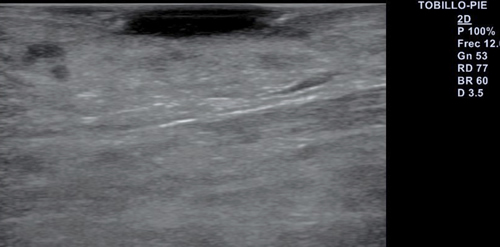

Se realiza exploración ecográfica vascular empleando para ello un equipo Alpinion E-cube 7 con una sonda lineal de 3-12 mHz, con una frecuencia de 12 mHz en la que destaca insuficiencia venosa y onda trifásica en arterias pedia y tibial posterior. Se realiza ecografía transulcerosa (Figura 2) mostrando área anecoica con punteado hiperecoico en su interior y con leve refuerzo acústico posterior, que afecta a la totalidad de la epidermis y penetra en dermis. Lesión bien delimitada, con ausencia de doppler en el interior de esta (Figura 3). Presenta una extensión ecográfica de 14 x 3.4 mm.

Figura 3. Ecografía transulcerosa con ausencia de doppler en el interior de la lesión.